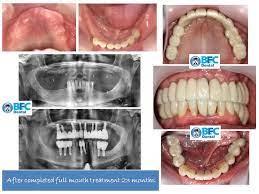

Résultats Avant / Après

Découvrez les transformations de nos patients